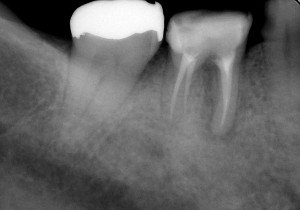

専用の器具とお薬を使いながら根の中の細菌感染をしっかり取り除いたところで、元々神経管があったところを専用の材料でしっかりと封鎖をし、細菌が再度感染しないようにしました。

↑根の治療終了後

その後は、歯の土台を作りしっかり補強した後、仮歯を入れて咬んでも痛くないか、歯肉の腫れは再発しないかなど経過観察をしました。